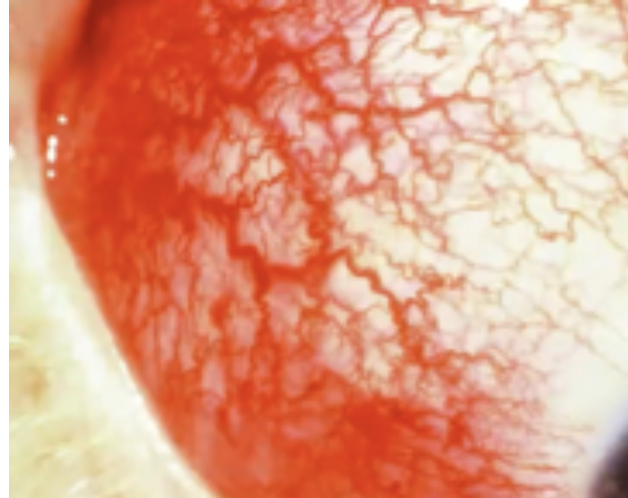

Diffuse Episcleritis

Abnormalities of the External Eye

Inflammation of the sclera

Conjunctivitis

Episcleritis

Abnormal Findings of 6. Inspect bulbar conjunctiva and sclera